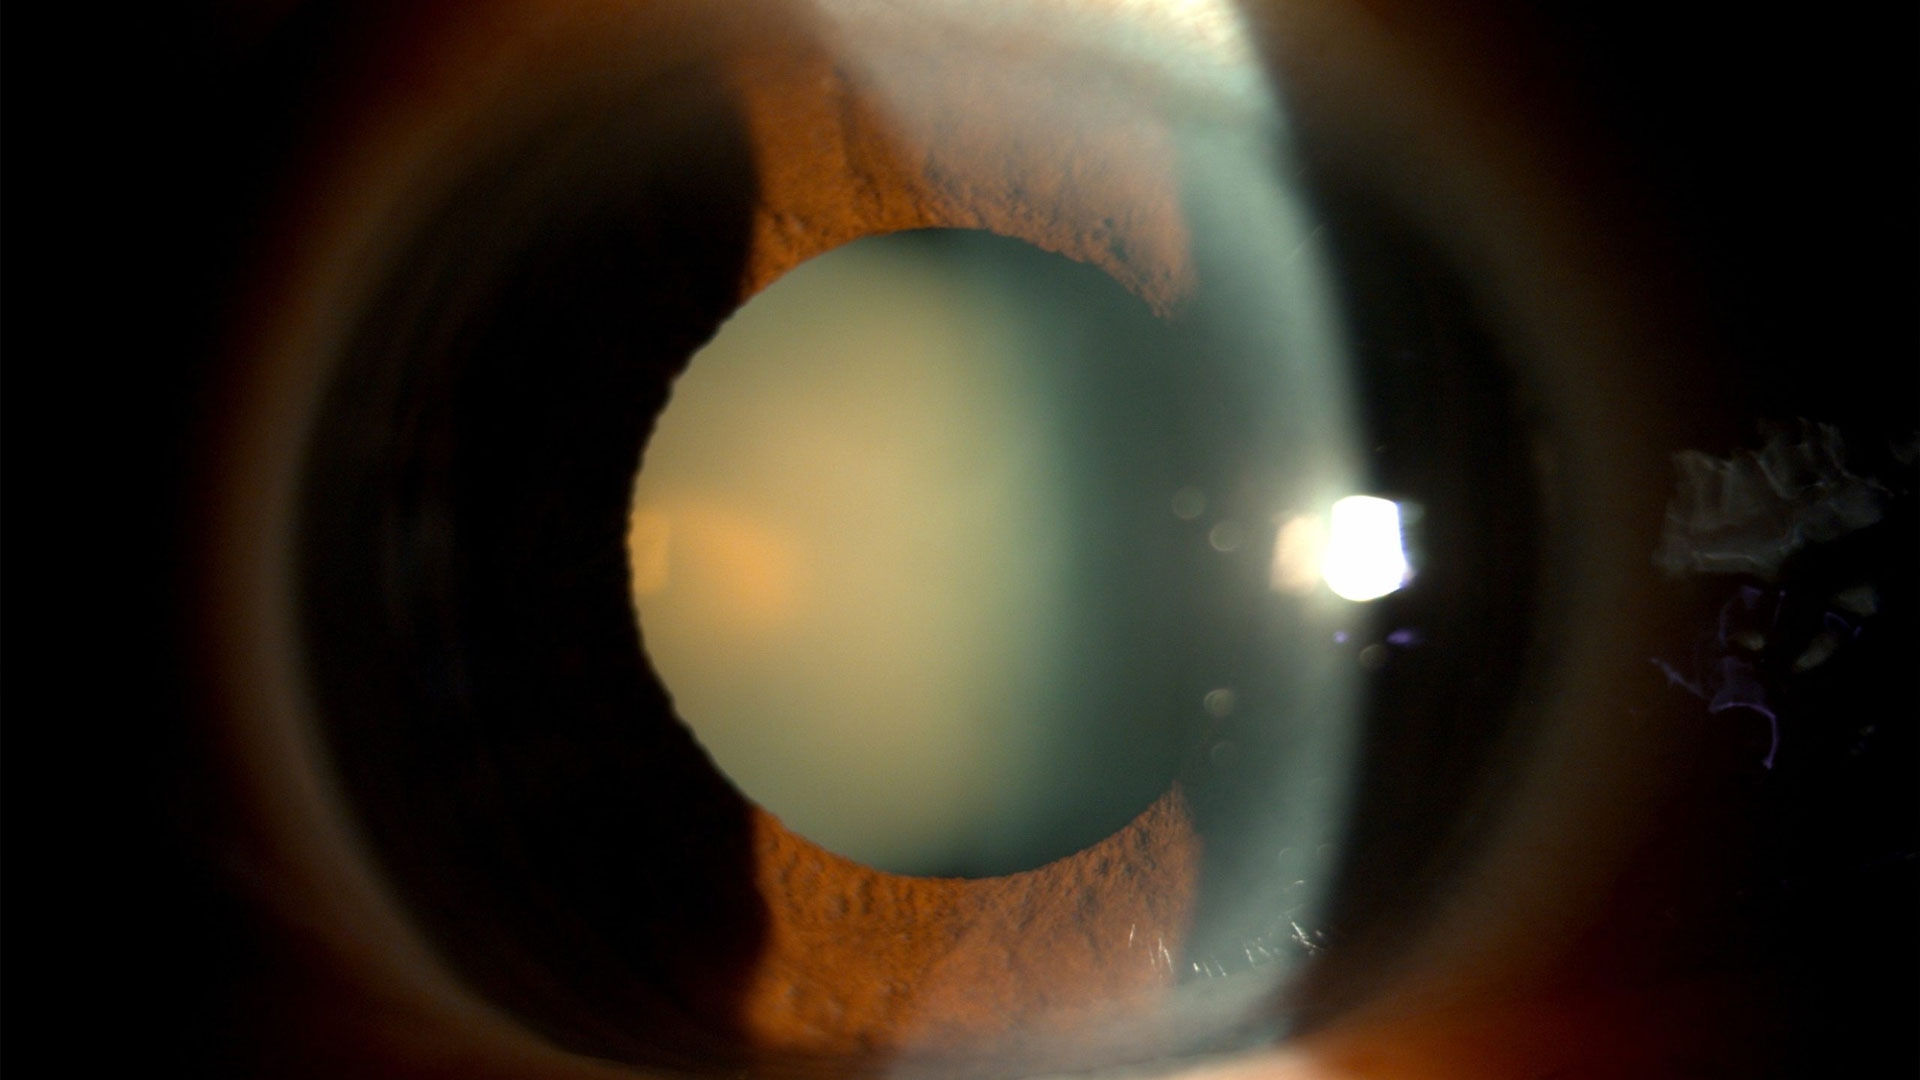

Katarakt cerrahisine yeni bir boyut kazandıran bu son derece gelişmiş lazer teknolojisi, kataraktın (gözün içindeki doğal merceğin buğulu bir şekilde örtülmesi ve sertleşmesi) çıkarılması ve görme bozukluğunu tedavi etmek için çıkarılan lensin yerine yapay bir merceğin implante edilmesi gibi hassas bir prosedürü içerir. Elde edilen sonuç, kataraktın geleneksel yöntemle çıkarılmasıyla aynıdır.

3 – Katarakt çıkarma

Son olarak, femtosaniye lazer kataraktı parçalamak için kullanılır ve cerrah bundan

sonra göz(ler)den kataraktlı dokuyu çıkarır.